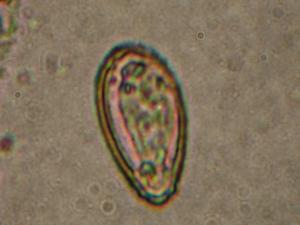

華支睪吸蟲蟲卵1.蟲卵檢查 糞便中找到蟲卵可以確診華支睪吸蟲病,檢出率約50%左右。常用的方法有直接塗片法、水洗沉澱法、改良加藤厚膜塗片法及醛醚法後2種方法檢出率較高。直接從十二指腸引流液中檢查蟲卵,檢出率接近100%因操作麻煩,增加病人的痛苦,不宜常規使用。

華支睪吸蟲蟲卵華支睪吸蟲蟲卵通過第一中間宿主(淡水螺螄)和第二中間宿主(淡水魚蝦)後發育成囊蚴,活的囊蚴被攝入後,經膽汁激活,囊內幼蟲破囊壁而出,經膽總管進入肝膽管發育為成蟲,亦可通過血管或穿過腸壁到達肝臟,最後寄生在肝膽管內發育為成蟲,成蟲的壽命一般為20-30年,主要寄生在人、犬、貓和豬的肝膽管內,蟲數多時亦可移居較大的膽管甚至膽囊內,偶爾在胰管內亦可發現成蟲。